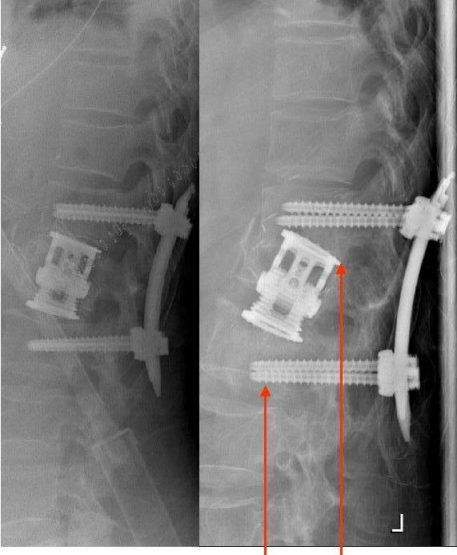

Figure 1: Left: Posterior bisegmental stabilization and anterior reconstruction after burst fracture of L1. Right: Septic implant loosening: Cage displacement and cut out of the distal pedicle screws after one year.

Figure 2: Temporary external posterior long segment stabilization (Hoffmann II external fixator, 5 mm pins). Surgical debridement of the anterior column and antibiotic chain spacer implantation.

Figure 3: Left: Procedural change. Internal posterior stabilization Th11/12 – L2/3 (Longitude/Medtronic; 6.5 mm pedicle screws). The antibiotic chains were left in situ. Because of the good bone quality, a pedicle screw augmentation was not necessary. Right: Removal of the antibiotic chains after further 4 weeks. Due to a progressive osseous bridging, there was no need for an anterior stabilization.